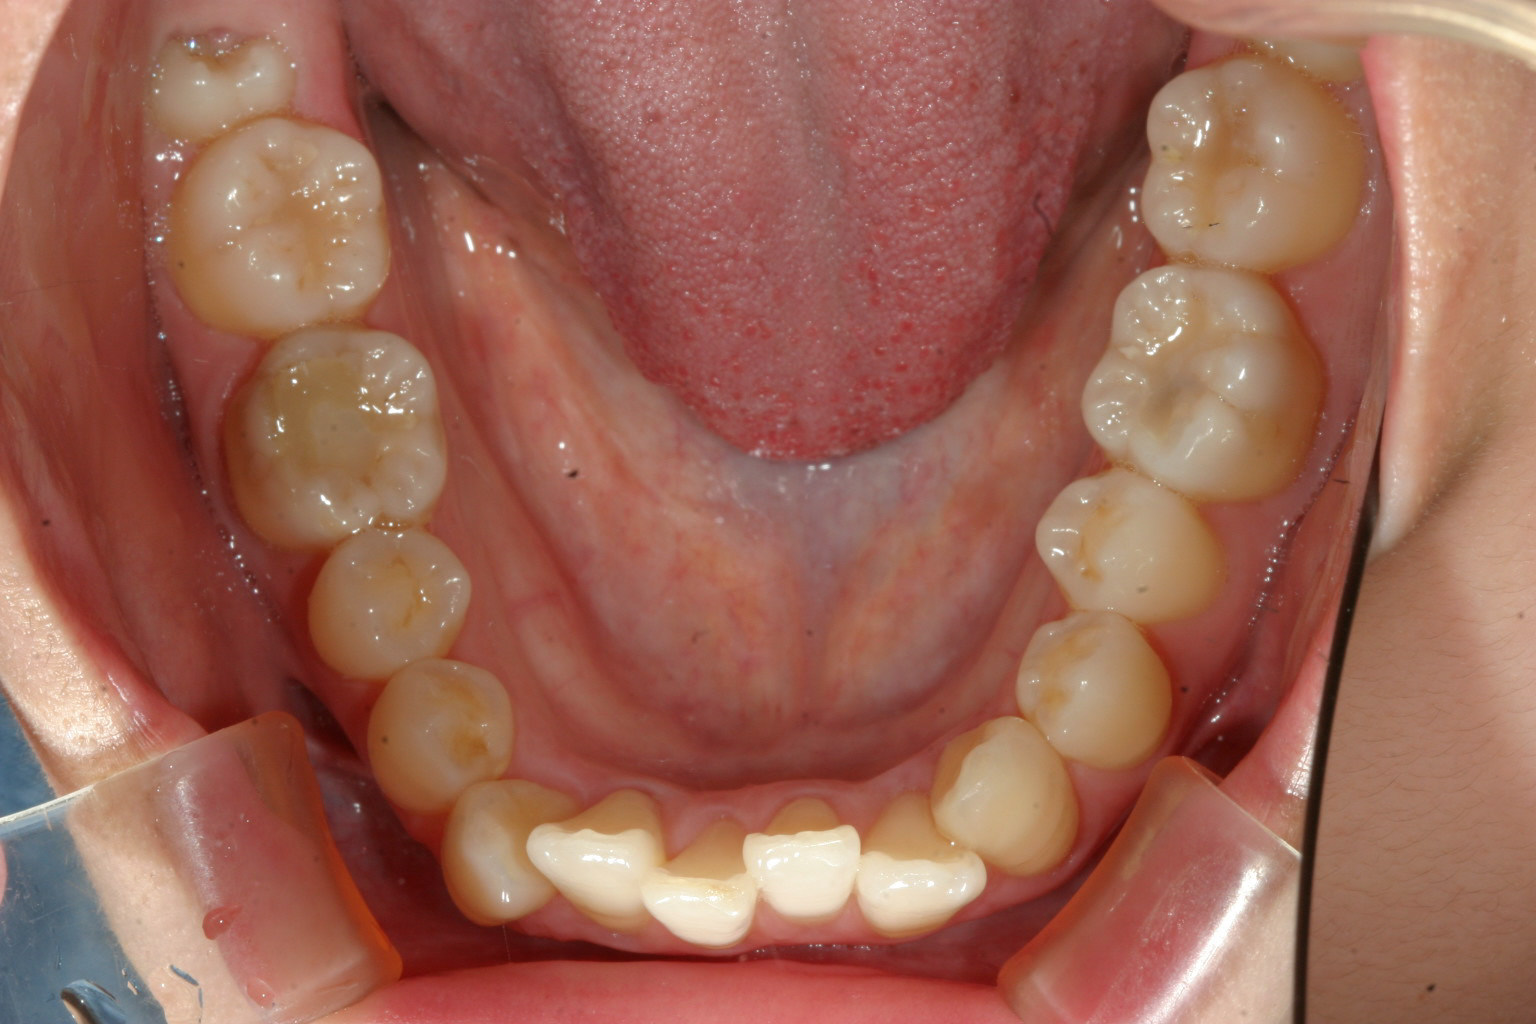

下の前歯は歯列がV字形の為4本の前歯が上手く並ばずガタガタになってます。

こちらも歯列をU字形にする事により綺麗に改善してます。

こちらの症例は典型的な症例で歯列形が悪い為の不正咬合です。

これって言って特別何をしたって事無く歯列を V字形をU字形にするだけでここまで改善します。